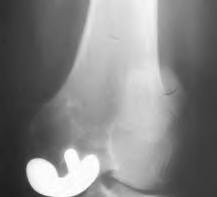

A 75-year-old man underwent total hip arthroplasty 10 years ago. He now reports mild groin pain which has been increasing lately. What is the most likely explanation for the finding in Figure A indicated with the arrows?

Osteolysis of the pelvis is a common complication associated with total hip arthroplasty. Osteolysis affects sockets with and without cement, and has been attributed to the biologic reaction to wear debris. With well-fixed cementless sockets, an expansile pattern of osteolysis is usually seen.

The radiographic appearance has a radiolucent area that starts at the implant-bone interface and expands into the cancellous bone away from the implant.

This pattern of osteolysis can be explained with the concept of effective joint space. This concept states that joint fluid and wear particles will flow according to pressure gradients and follow the path of least resistance.